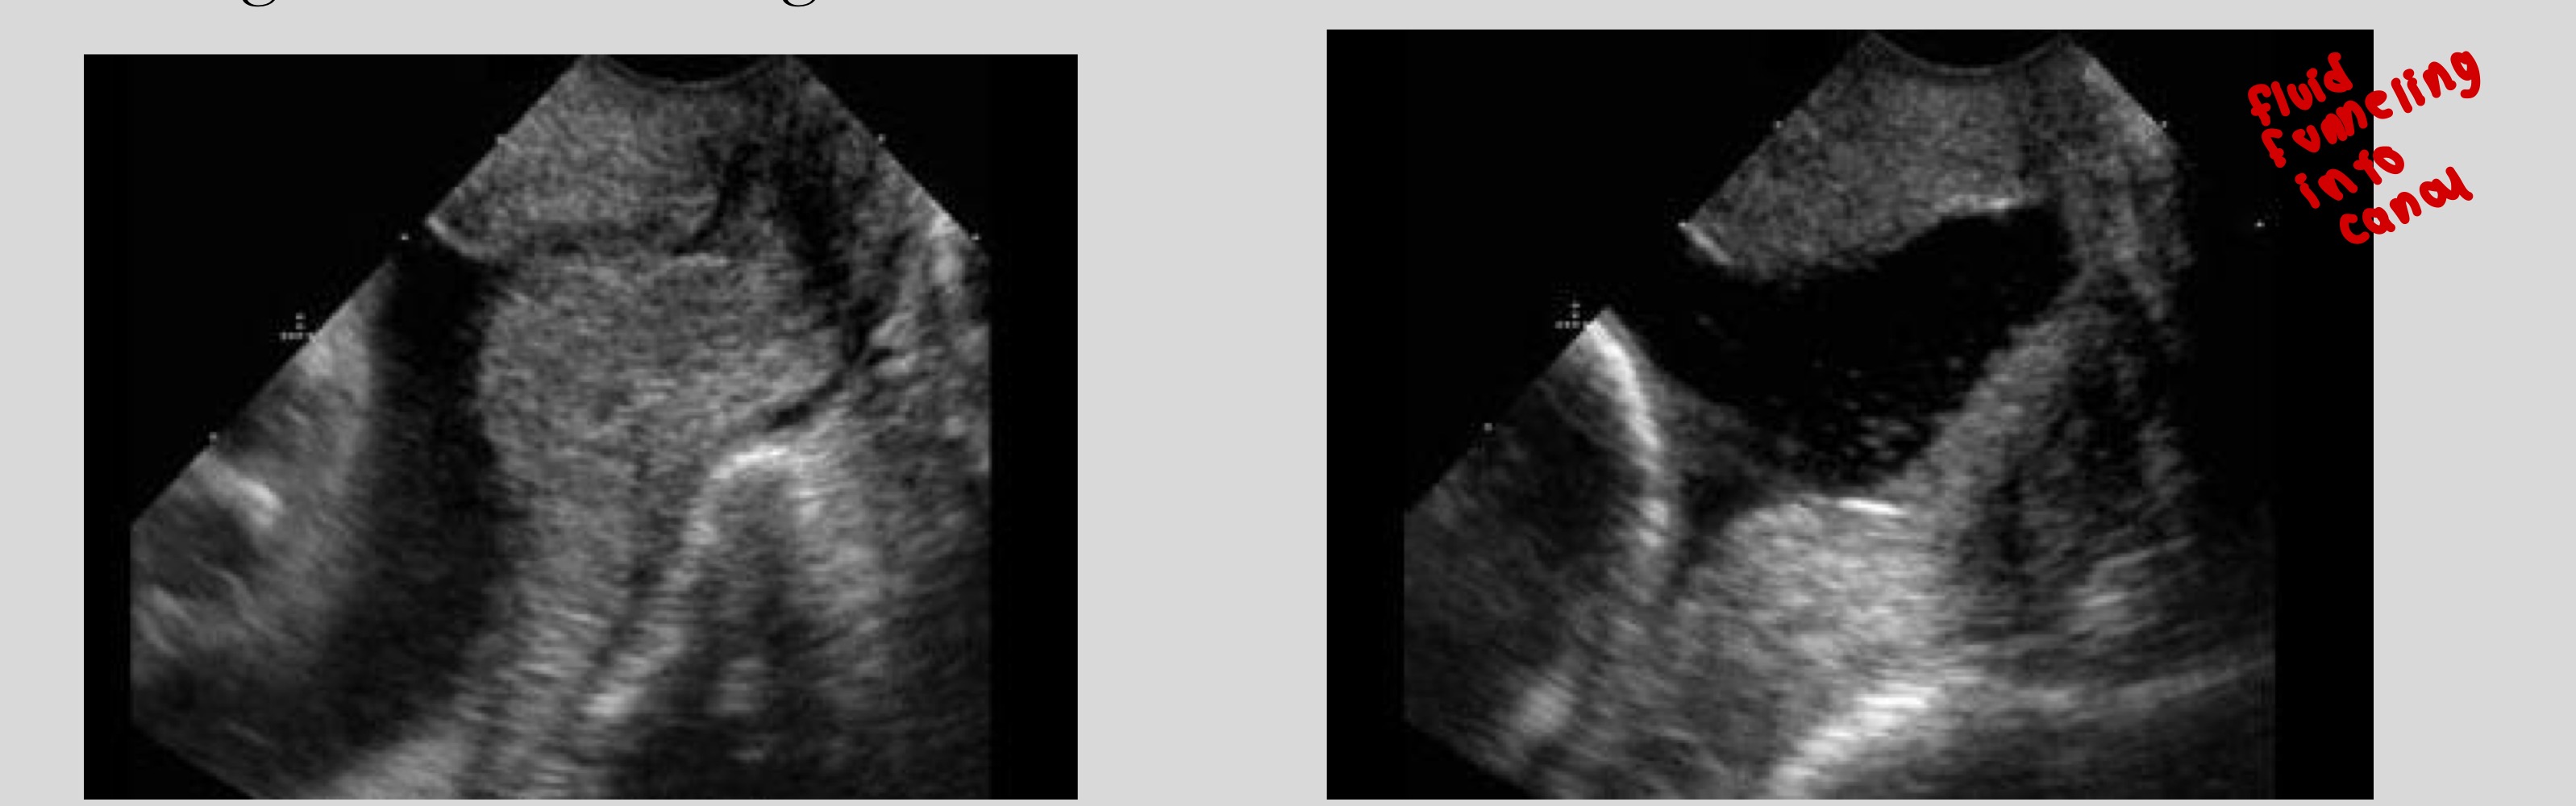

What should you do if you see funneling during scanning

Apply fundal pressure and wait to rule out contraction

Why should you wait if funneling is seen

It may be due to a temporary uterine contraction

What is funneling

Dilatation of the internal os with shortening of cervical length

What shapes can funneling appear as

U-shaped or V-shaped

Which funnel shape is associated with higher risk of preterm delivery

U-shaped funnel